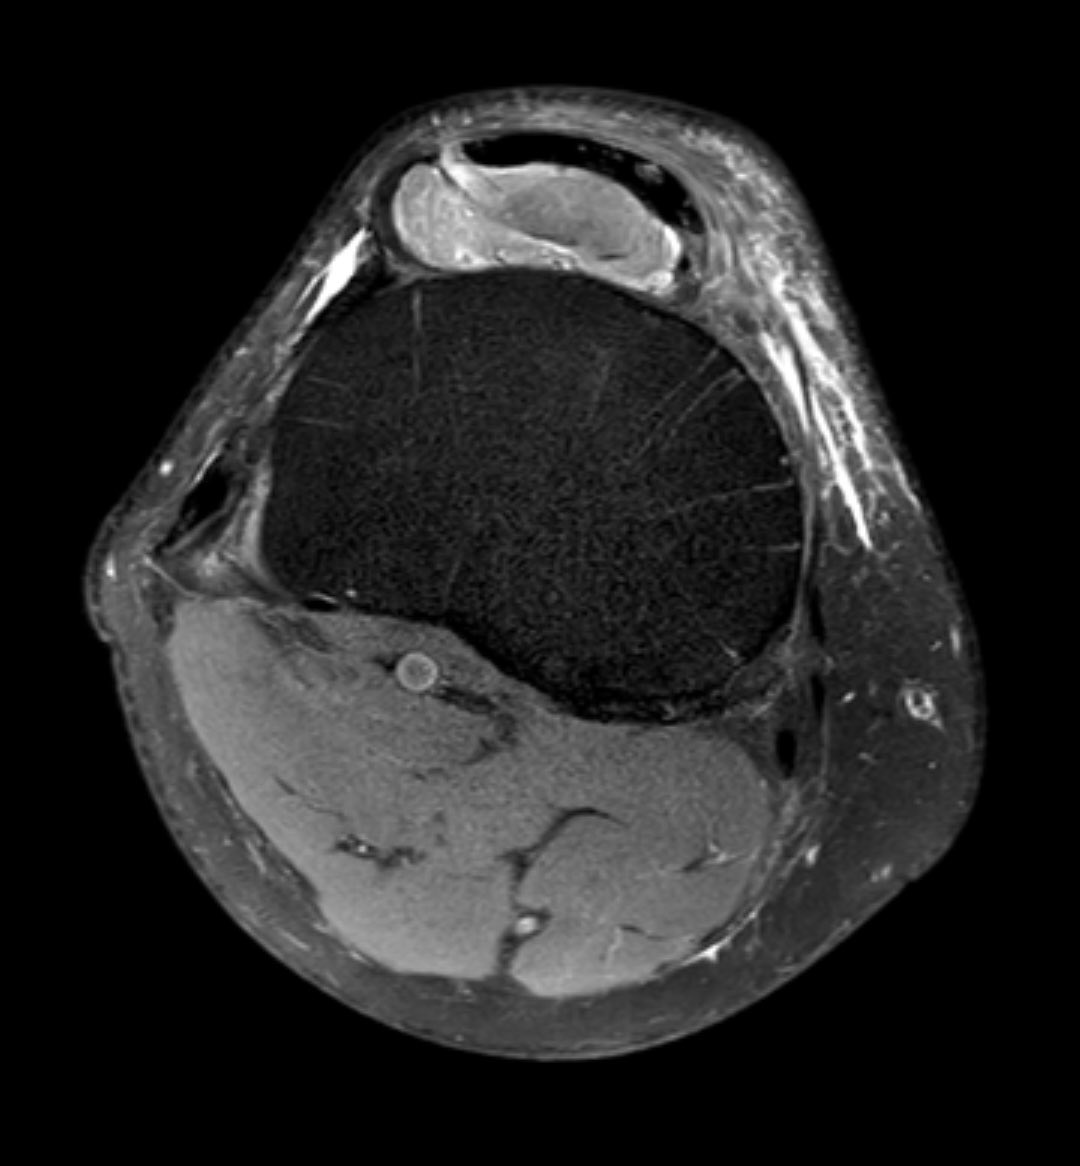

#CaseOfTheWeek‼️🥳‼️ ☢️🩻☠️Case#22☠️🩻☢️ #Mass 📲➡️➡️#Diagnosis❔❓❔ #FOAMRad #RadEd #MedEd #OrthoEd #OrthoTwitter @ssr_rwg @UWRadRes @ISSVA_org